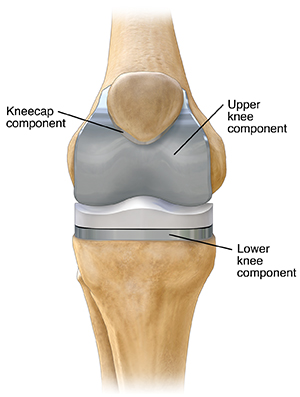

Your orthopedic surgeon will put your new artificial knee in place after the damaged bone and cartilage of your knee are removed.

The two most common types of knee prostheses used in knee replacement surgeries are cemented prosthesis and uncemented prosthesis. Sometimes a combination of the two types is used. A knee prosthesis is made up of metal and ceramic or plastic. A cemented prosthesis is attached to the bone with a type of epoxy. An uncemented prosthesis attaches to the bone with a fine mesh of holes on the surface. The bone grows into the mesh and attaches to the prosthesis.

The prosthesis (artificial knee) is made up of these three components:

Tibial component.This replaces the top of your shin bone (tibia).

Femoral component.This replaces your two thighbone (femoral) condyles and the patella groove.

Patellar component.This replaces the bottom surface of the kneecap that rubs against your thighbone.